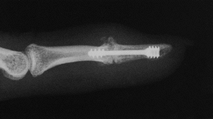

They provide stable fixation, are relatively uncomplicated technically,

and may be used in conjunction with cup and cone, miter, or straight

cut techniques. They allow easier adjustment of the arthrodesis site

than many other techniques. Both techniques are excellent for the

patient with rheumatoid arthritis, in whom inadequate bone stock may

not allow screw techniques.

Figure 72.3. Metacarpophalangeal joint fusion with Kirschner wire fixation, lateral view.

Figure 72.4. Metacarpophalangeal joint fusion with Kirschner wire fixation, AP view.